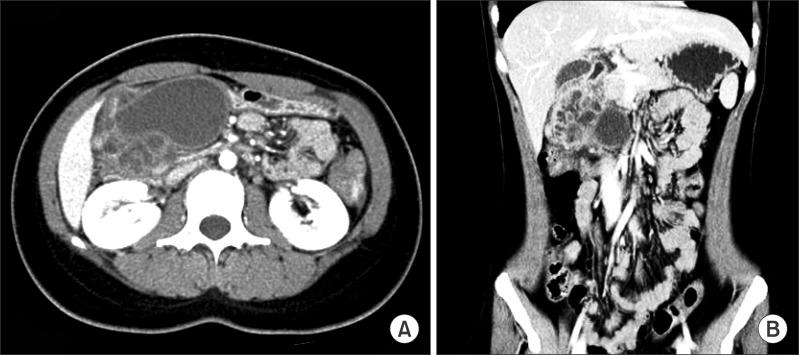

A 21-year-old woman presented gastrointestinal manifestation showing intermittent abdominal pain, nausea, and vomiting. An upper endoscopic examination showed round, elevated mucosa at the antrum of the stomach anterior wall. After CT scanning, a huge degenerated gastrointestinal stromal tumor was suspected. Subtotal gastrectomy with Billroth II anastomosis was performed. Histologically, pseudocystic degeneration of the heterotopic pancreas was confirmed. The patient showed eventful postoperative course except temporary dilated gastric emptying. The patient is doing well without any abnormal symptom at 8-month follow-up. This report is a rare case of gastric outlet obstruction caused by a pseudocyst originating from a heterotopic pancreas in the gastric antrum.

一名21岁女性出现胃肠道症状,表现为间歇性腹痛、恶心和呕吐。上消化道内镜检查显示胃前壁 antrum 处有圆形隆起的黏膜。CT扫描后,怀疑是巨大的退化性胃肠道间质瘤。进行了毕Ⅱ式吻合的胃次全切除术。组织学检查证实为异位胰腺的假囊肿变性。除了暂时的胃排空延迟外,患者术后病程平稳。在8个月的随访中,患者情况良好,无任何异常症状。本报告是一例罕见的由胃窦部异位胰腺起源的假囊肿引起胃出口梗阻的病例。